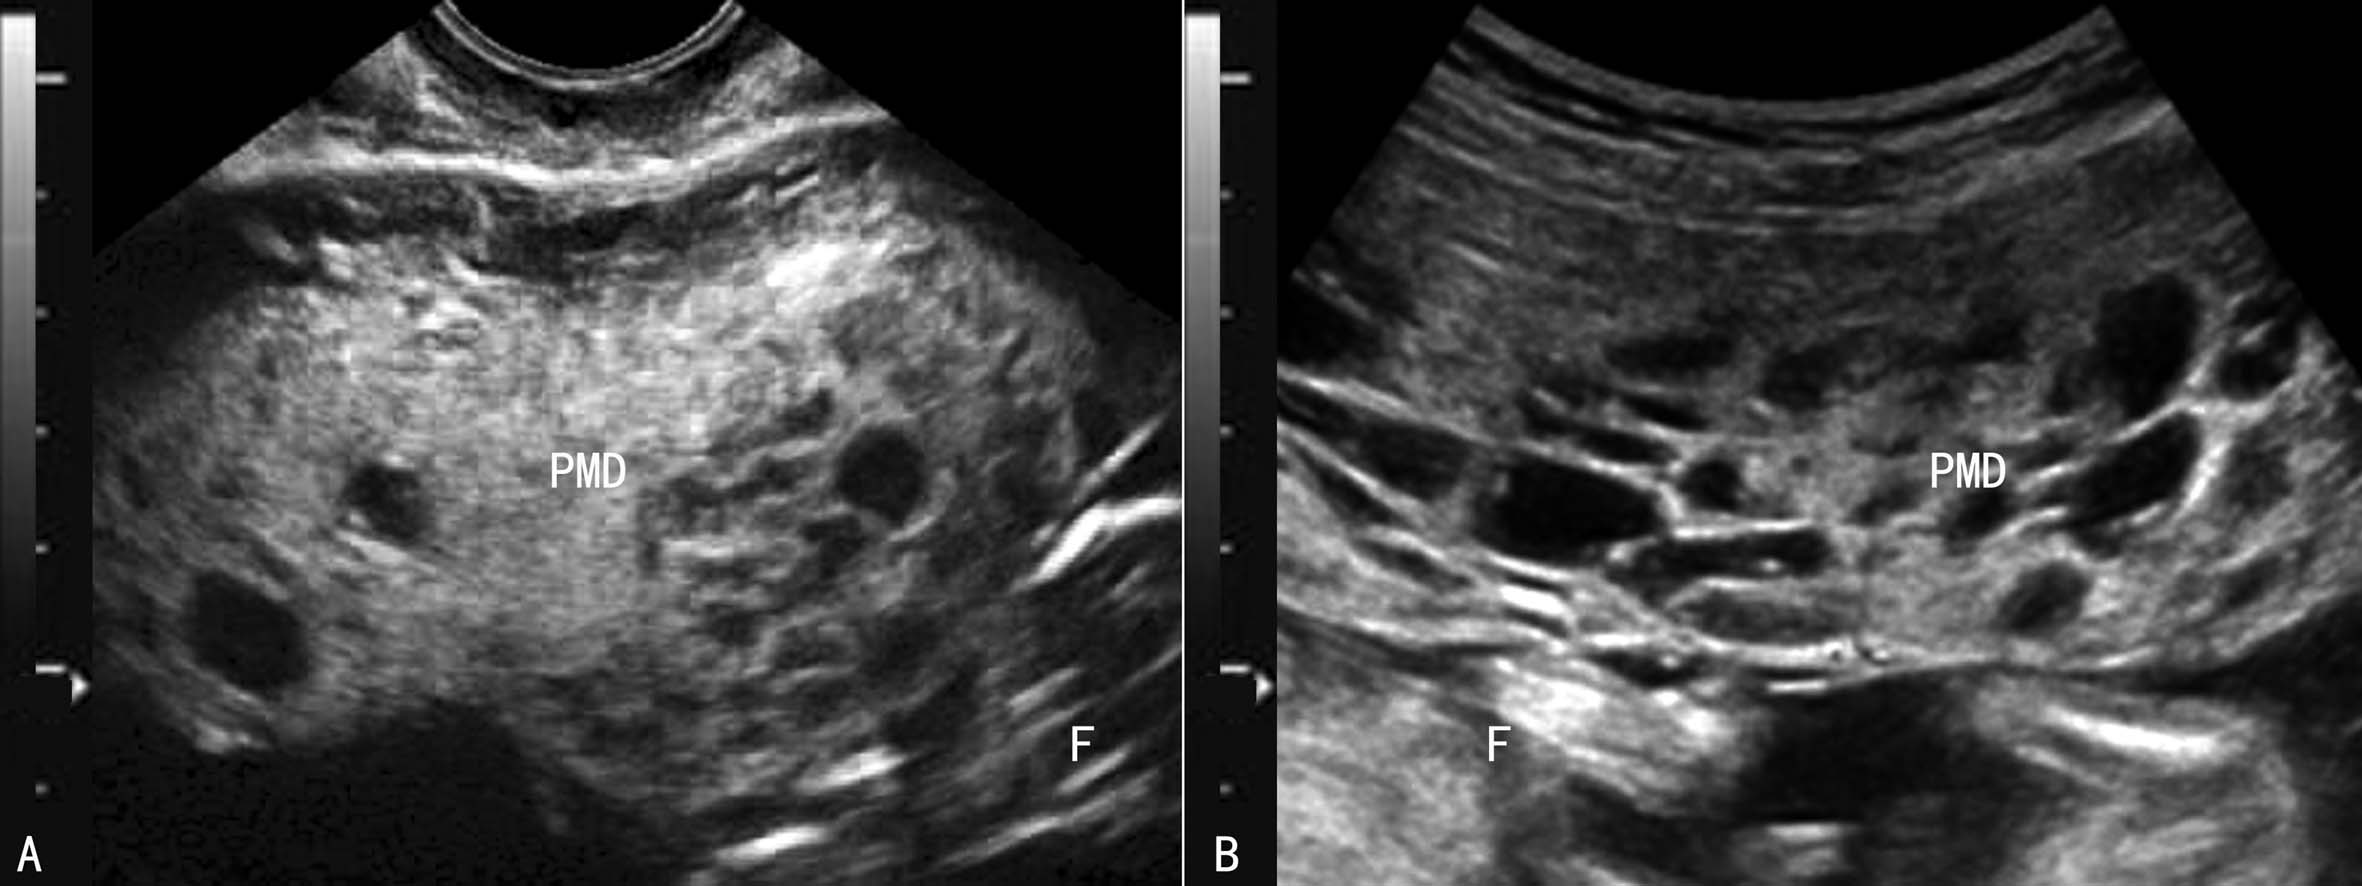

胎盘间质发育不良(PMD)是一种少见的良性病变,发生率大约为0.02%。PMD发生的原因还不清楚。有些病例发现绒毛间质增生、绒毛膜血管扩张,部分可见与胎盘血管瘤Beckwith-Wiedemann综合征(突眼-巨舌-巨人综合征)并存,故而考虑PMD可能与中胚层的发育异常及染色体异常有关。PMD的临床表现不确定,已经报道的PMD可能并发胎儿生长受限、羊水过多、早产、胎儿溶血性贫血、胎儿血小板减少症、胎儿宫内生长受限、胎盘早剥、先天性畸、死产等。

2D-US最早有报道在11孕周发现胎盘异常回声(图4A),显示为胎盘较正常增大,部分区域可见蜂窝状无回声(图4B),CDFI检查显示血流增多,声像图表现类似葡萄胎,胎儿发育未受到影响,孕妇血hCG在正常范围内,而AFP则显示增高。此后PMD声像图显示逐渐明显。2D-US显示胎盘增厚、增大,内部显示蜂窝状无回声,可以是部分性或占据整个胎盘(图4、图5),需要注意与绒毛血管瘤、胎盘出血、胎盘梗死以及不全流产水泡样等变进行鉴别。超声多普勒血流显像检查对PMD与葡萄胎、胎盘出血、胎盘梗死的鉴别很有价值。葡萄胎时病变内部常显示丰富的血流,PW检查可以记录到高速、低阻力血流频谱;胎盘血管瘤多显示为胎盘胎儿面凸向羊膜腔的局限性回声,边缘清楚,内部回声强度不等,分布不均匀,内部如果有血流显示,则其血流性质与脐带血流一致;PMD也可以显示为局部的瘤样回声,但内部血流较少或没有明显血流显示,也不能记录到类似脐带的低阻力血流频谱。

图4胎盘间质发育不良